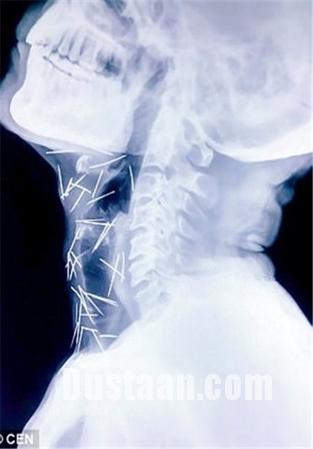

ادامه مطلب »وجود ۷۵ سوزن در بدن این مرد هندی! +تصاویر

پزشکان با مراجعه مردی جوان به بیمارستان که عنوان داشت در ناحیه گلو و کف پایش احساس درد دارد، اقدام به عکسبرداری از وی کردند، انها در کمال تعجب مشاهده …